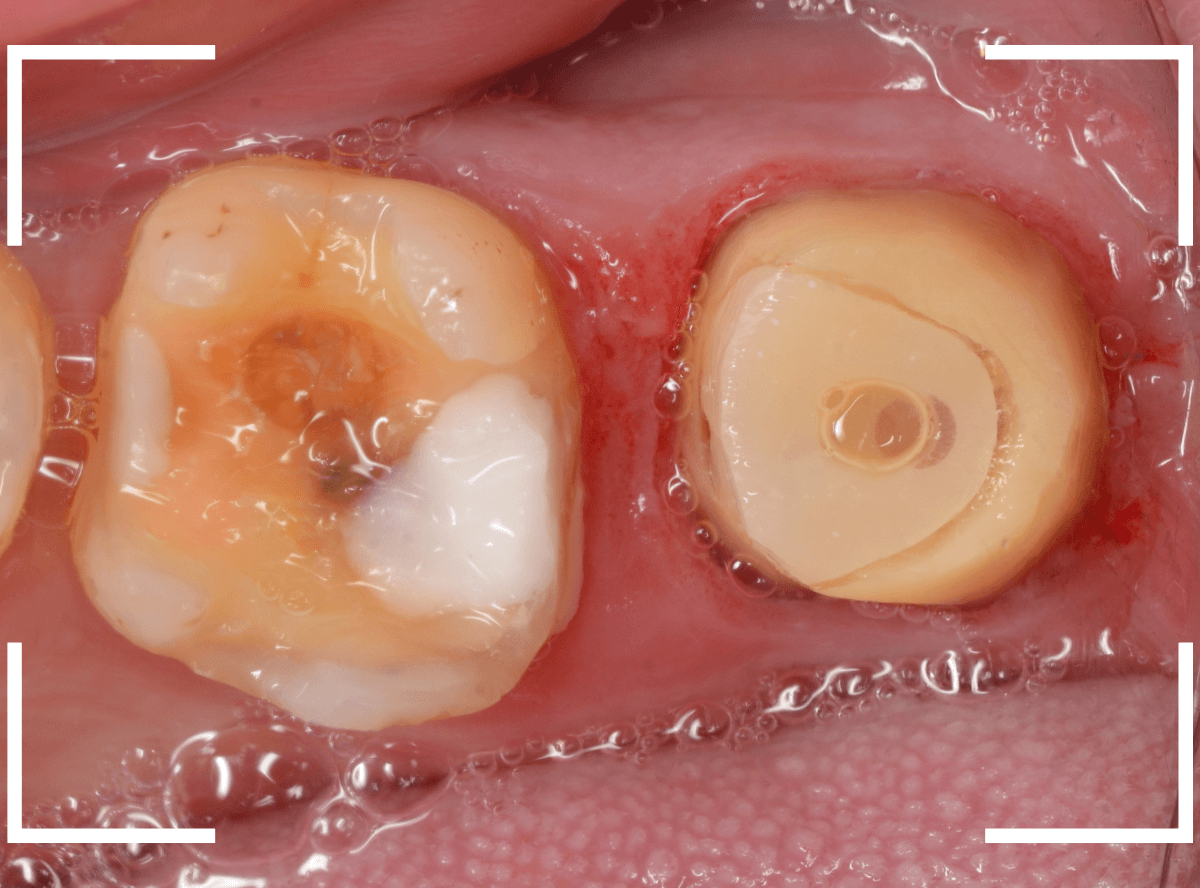

さし歯の土台の補修と、おやしらずの虫歯の処置をしたところです。

この状態で型をとります。